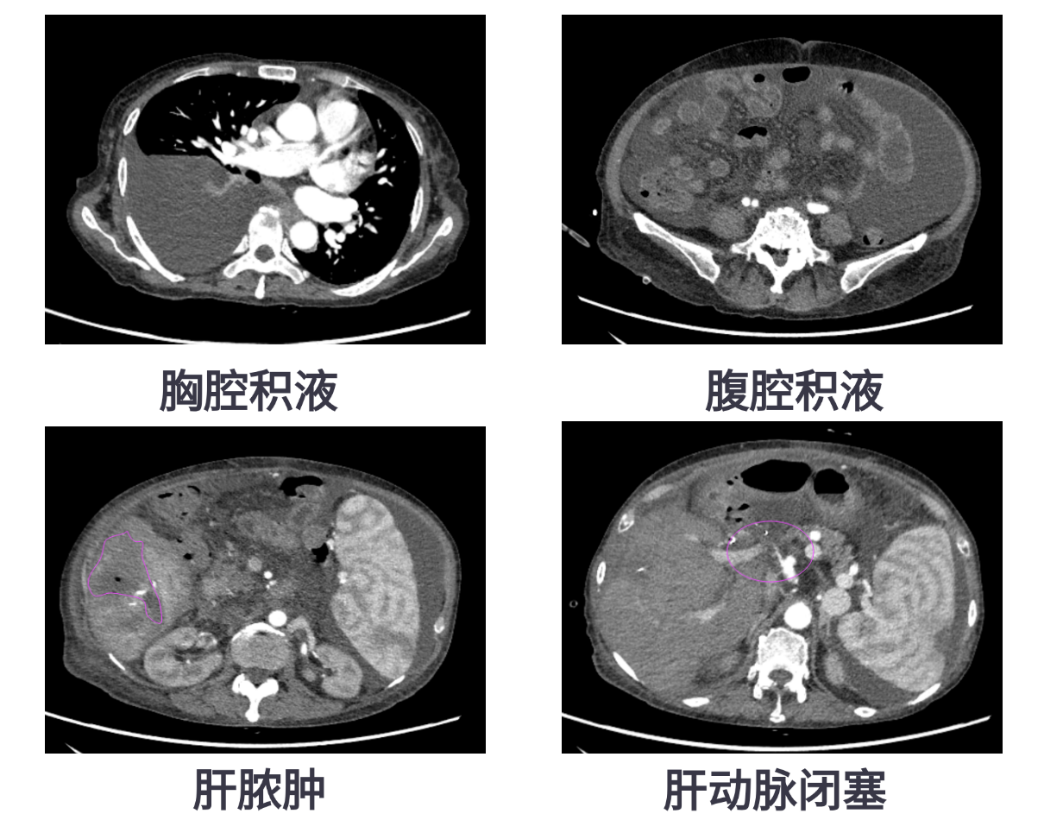

肝移植是治疗终末期肝病的重要手段,但术后并发症仍不容忽视,尤其是肝脓肿,一旦反复发作,不仅影响患者生活质量,更威胁移植肝的存活。63岁的患者王女士因自身免疫性肝硬化曾接受肝移植手术。术后6个月,她出现发热,检查发现肝脓肿、大量腹腔积液和胸腔积液,在外院进行穿刺引流后症状缓解,但不久后便再次发热。

转入我院后,CT显示患者肝脏包膜下积气、肝右叶低密度影,提示脓肿复发,同时存在门静脉高压、脾大、肝动脉狭窄等复杂情况。医疗团队决定为她实施经导管脾动脉栓塞术(SAE),并同期进行肝动脉造影和压力测量。

肝移植后,肝脏的血流供应依赖于肝动脉和门静脉。如果出现肝动脉狭窄或血栓,会导致肝脏供血不足,尤其是胆管的血供几乎完全依赖肝动脉。一旦缺血,容易引发胆道损伤、感染,甚至肝脓肿。此外,门静脉血流过多(门静脉高灌注)也会通过“肝动脉缓冲反应”抑制肝动脉血流,进一步加重缺血。这种情况下,即使使用强效抗生素或穿刺引流,也容易反复感染。